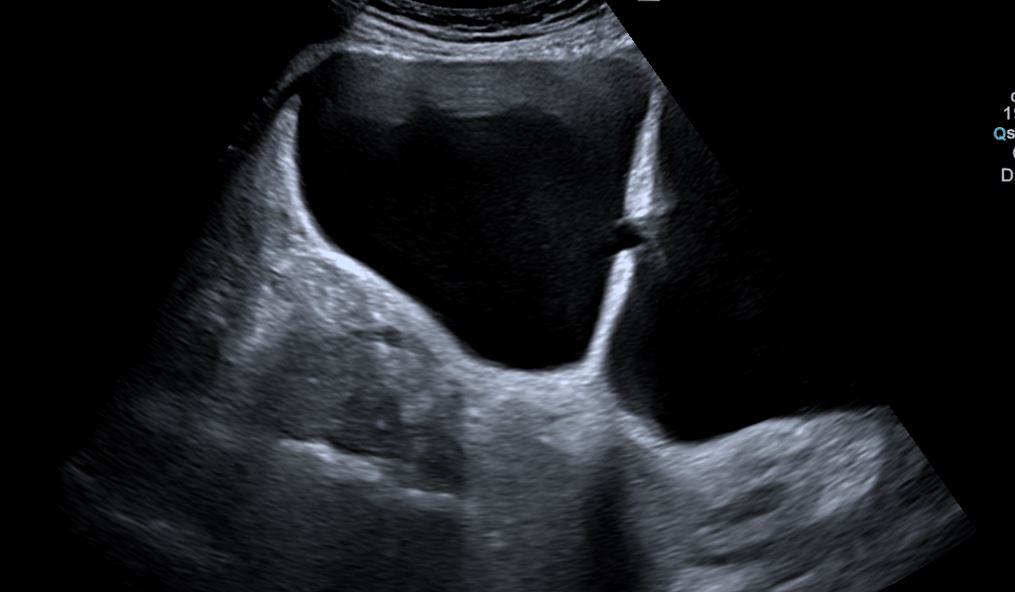

Riñones de tamaño y morfología normales. No observamos litiasis ni dilatación de la vía urinaria. A nivel de la vejiga presenta un tabique con comunicación a una gran cavidad en la pared lateral derecha que da la impresión de que existen dos vejigas urinarias. No hay lesiones parietales. Próstata 32 cc. Volumen premiccional de la cavidad mayor 350 cc y posmiccional 210 cc.

Vejiga urinaria con presencia de jets ureterales, de paredes lisas con un gran divertículo en la pared lateral derecha de 543 cc premiccional que vacía a la mitad en posmiccional 310cc (57%).Volumen vesical premiccional 620cc y posmiccional 179 cc (28%).